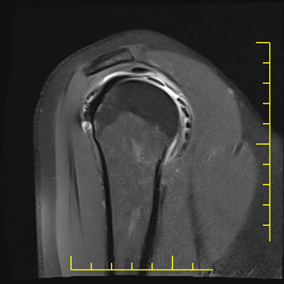

22. veljače 2026.Artrografija zglobova je specijalizirana dijagnostička metoda kojom se uz primjenu kontrastnog sredstva detaljno prikazuju strukture unutar zgloba – hrskavica, labrum, ligamenti, kapsula i tetive.

Artrografija je dijagnostički postupak u kojem se pod kontrolom RTG-a ili ultrazvuka u zglob aplicira kontrastno sredstvo, a zatim se izvodi magnetska rezonancija (MR) ili kompjutorizirana tomografija (CT).

Artrografija kuka

MR artrografija kuka posebno je važna kod sumnje na oštećenje acetabularnog labruma i femoroacetabularni impingement (FAI).

Najčešće indikacije

- bol u preponi bez jasnog uzroka

- sportske ozljede kuka

- sumnja na labralnu leziju

- rana degenerativna oštećenja

- planiranje operativnog zahvata

Prednosti u odnosu na standardni MR

- bolja vizualizacija labruma

- jasnije definirane pukotine hrskavice

- preciznija procjena intraartikularnih lezija

Kod mlađih pacijenata s bolovima u kuku artrografija može otkriti rane promjene koje još nisu vidljive na klasičnoj magnetskoj rezonanciji.